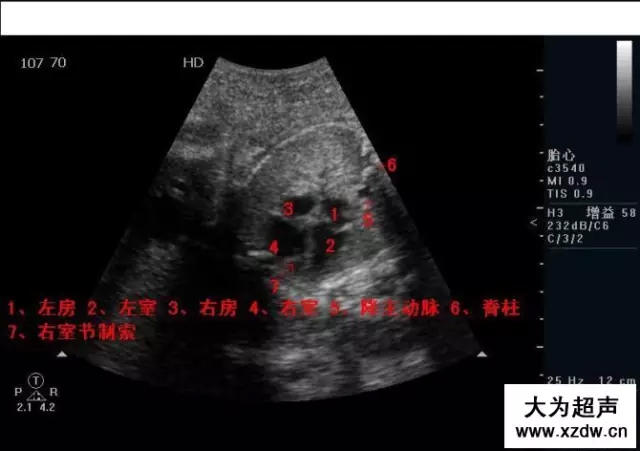

產科超聲正常圖片